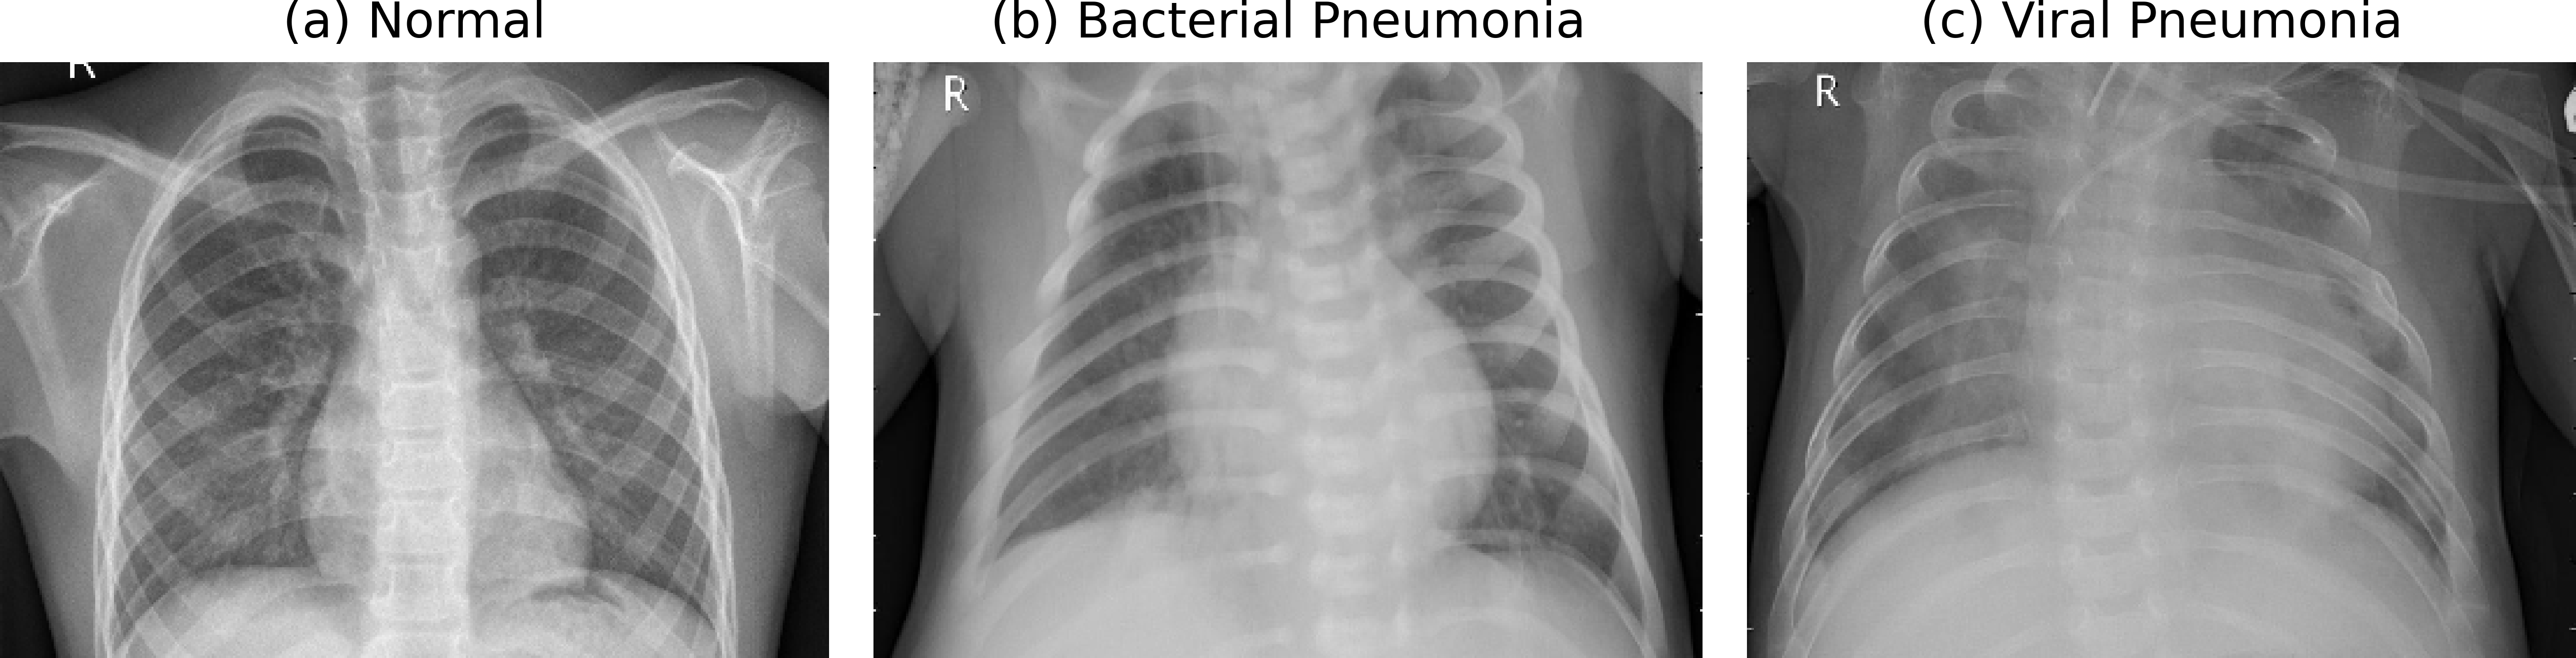

We used the publicly available Chest X-ray dataset [KERMANY2018]. In this dataset, 1583 X-ray images are in normal class and 4273 are in pneumonia class including both train and test set. In train set 1349 images are in normal class and 3884 images are in pneumonia class. Similarly, in test set 234 images are in normal class and 390 images are in pneumonia class. However, during dataset inspection, we observed that some patients ids were on both training and test sets, which could cause data leakage. To address this issue, we merged the original splits and re-partitioned the dataset at the patient level into training (70%), validation (15%), and test (15%) sets. Each image was resized to 224 x 224 pixels to match the input requirements of ImageNet-pretrained backbones. Since the original images were grayscale, we duplicated the channel three times to create a pseudo-RGB input to match the input shape for pretrained backbones. Further, to enhance generalization, we applied data augmentation including random rotation, horizontal flipping, brightness/contrast adjustment, and Gaussian noise. Dataset splitting was performed at the patient level to prevent data leakage, with 70% of patients for training, 15% for validation, and 15% for testing.